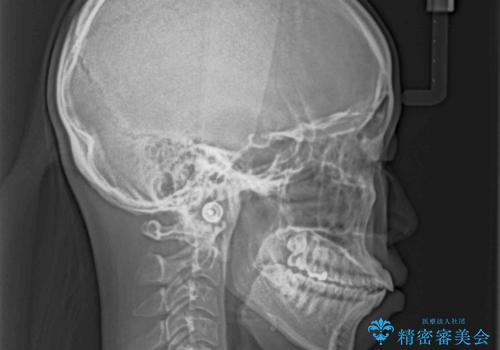

- くちばしのように飛び出した前歯を気にして来院された患者様です。

上下左右の第一小臼歯4本を抜歯して、ワイヤー装置にて矯正治療を行うこととしました。

舌の突出癖により、口元が突出しているだけでなく、上下前歯が非接触となっておりました。

舌のトレーニングをしっかりと行っていただくことで、2年を切って治療を終えるとともに

、上下前歯を接触させることができました。